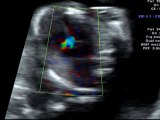

Canale atrio - ventricolare

Ecocardiografia fetale : doppler normale

Canale atrio - ventricolare completo